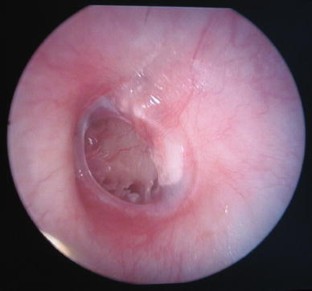

Fig. 1